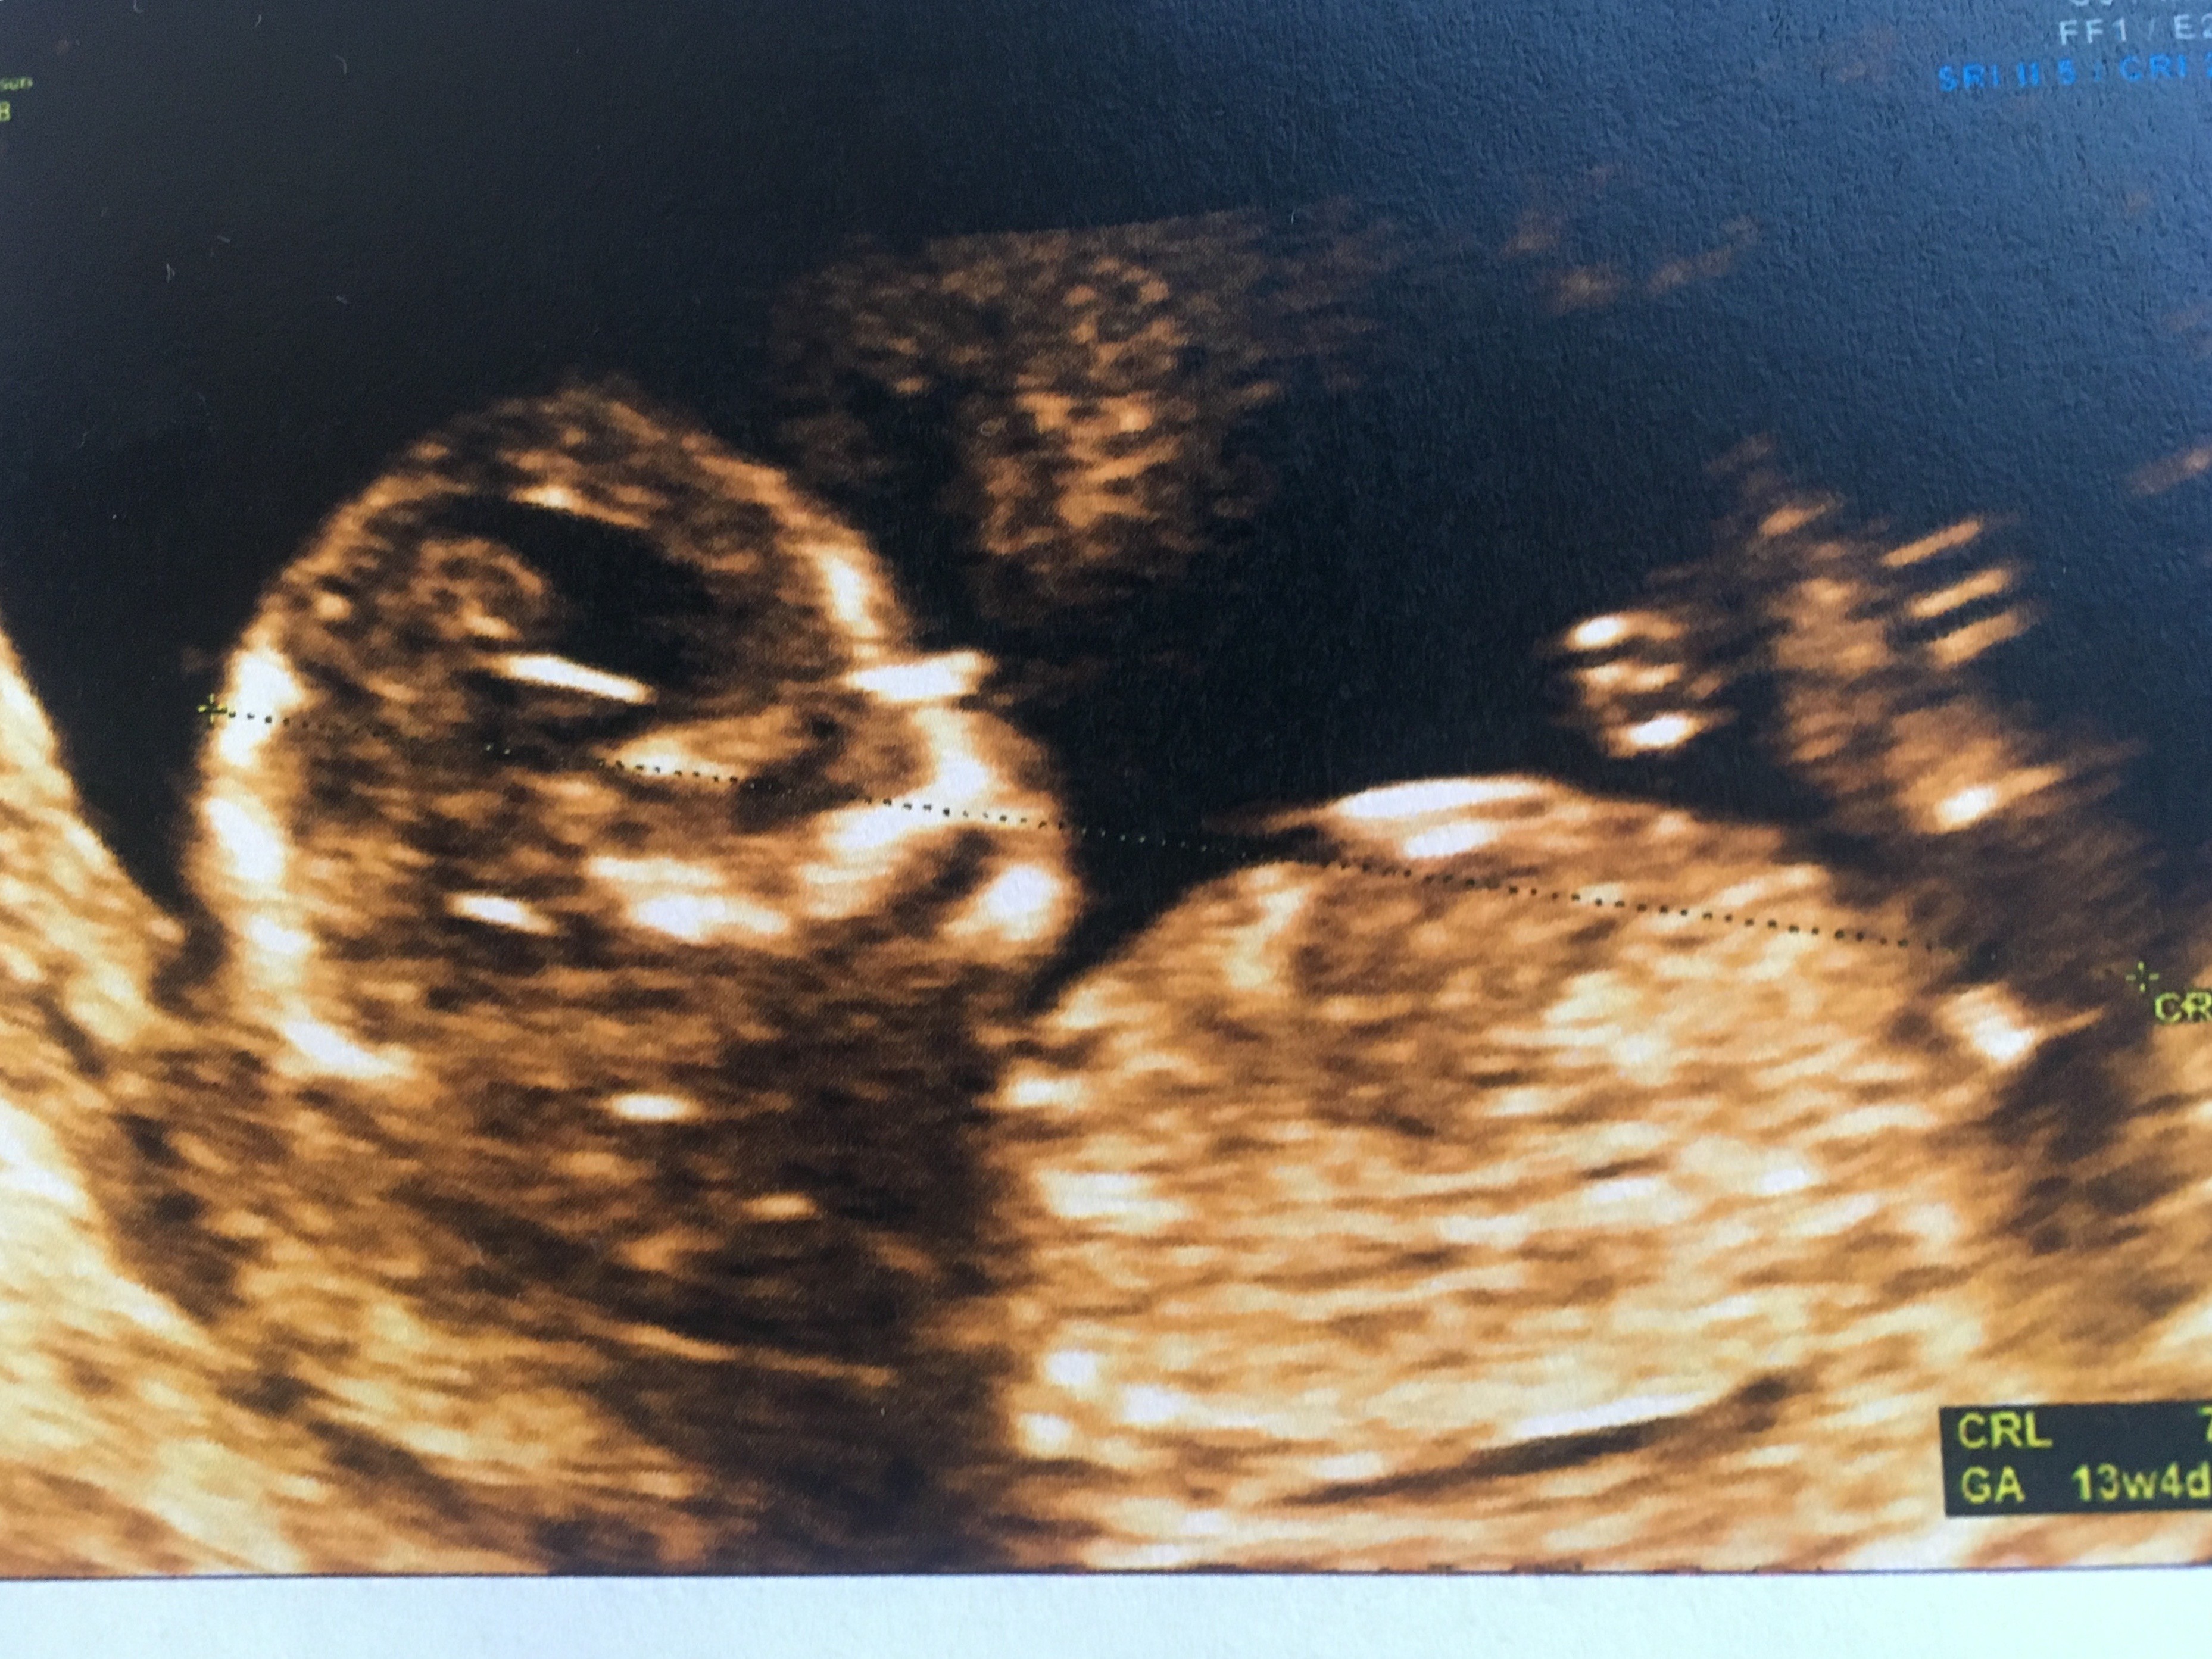

Rozwiązanie

Cześć dziewczyny proszę was o ocenę zdjęcia usg... Miesiąc temu zapowiedzieli mi syna a 4 grudnia na połówkowym ze córka... Trochę mam mętlik w głowie 😞

I czy ten „cypelek”na nubie o czymś świadczy czy maja go zarówno chłopcy jak i dziewczynki

Zżera mnie ciekawość, choć gdzieś w środku czuje ze druga córa się szykuje zamiast synka...

Załączniki

• E622F8B3-4E12-4F76-A34E-879251B1E76F.jpeg

E622F8B3-4E12-4F76-A34E-879251B1E76F.jpeg

295,3 KB · Wyświetleń: 416